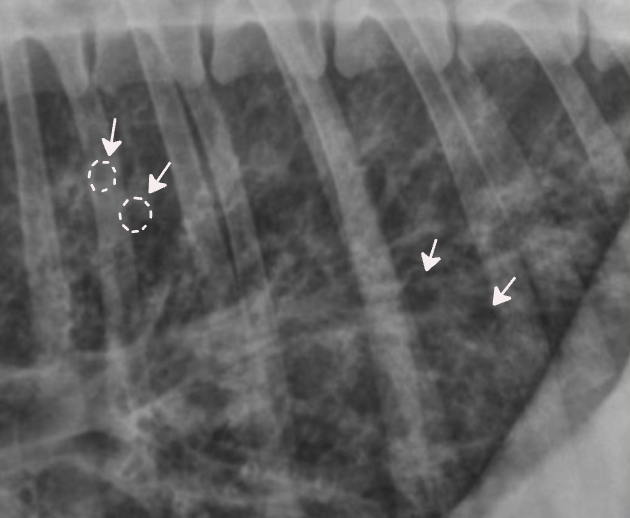

✳️ Bronchial pattern (기관지 패턴)

염증 세포 침윤으로 기관지벽 두꺼워짐

- Doughnut sign : end-on

- Tramline sing : side-on

원인

- Bronchitis (만성)

- Allergic (Feline asthma, 알러지성 폐렴)

- Immune-mediated (PIE)

주의

- 보인다고 해서 무조건 질병은 X

- 말단에서 다수 관찰되면 질병 가능성 ↑